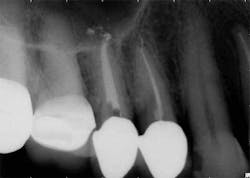

The success of endodontic treatment is directly related to the clinician’s ability to remove maximum numbers of bacteria from the root canal system. (1,2) If we can agree that all root canal treatment is associated with a certain degree of skill and precision in spite of perceived ease of treatment, I think it is fair to say there are no easy root canals. Some teeth are more difficult than others due to access limitations or anatomy, but the problem that faces all of us, in every tooth, is our inability to measure the absence of bacteria within the root canal and the potential for microanatomy to exist at any level of the root—whether it is a five-canal molar or a single-rooted anterior. It is impossible to determine the exact terminus of the root canal system, and there is no uniform agreement about where the root canal system ends. (3,4) The use of an apex locator can aid in this determination, but there is often disagreement between radiographic information and an apex locator, even in single-rooted anterior teeth, because the canal terminus can be at the radiographic apex or as much as 3 mm from it. (5) All instrumentation techniques leave a certain amount of the canal wall untouched, and we are not able to sterilize the root canal system. (6,7) The apical portion of any tooth may have dentinal tubules that can harbor bacteria, and the concept of a single uniform canal opening at the apex is anything but accurate. (8,9) Many teeth will have multiple portals of exit that may or may not be present in the apical third of the root. (Figure 1) As a result, the clinician must assume the apical canal anatomy in every tooth is highly variable in size, shape, and number (10,11,12) and there are no “easy ones.”

maxillary central incisor with a necrotic pulp. A prominent lateral canal can be seen,

but there is no way to know if multiple microscopic branches are present at any level

of the root canal system.